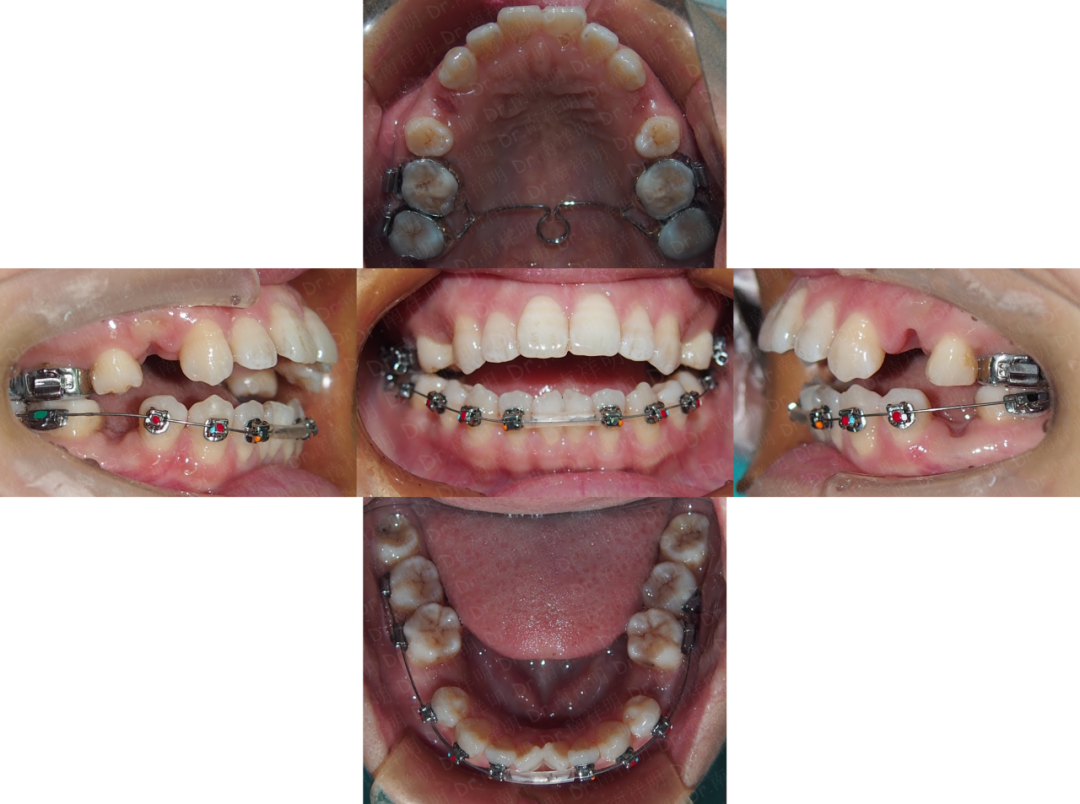

治疗结束

矫治结束口内相

上下牙列已排齐

拔牙间隙关闭

上下前牙开合已纠正,覆合覆盖正常

上下中线对齐

尖牙、磨牙达中性关系

后牙覆盖正常

采用透明压膜保持器和哈雷氏保持器保持

唇舌肌肉训练继续!

矫治前后口内对比

心得体会

本案例畸形表现与患者舌不良习惯息息相关,因此矫治前宣教,坚持唇舌肌训练,对于矫治过程、最后的效果,以及后续的稳定性,都起着至关重要的作用,因此从开始到结束,再到保持,肌肉训练一直贯穿始终!

患者开合的解决,主要利用了后牙主动垂直向控制,磨牙中度支抗设计、后牙近中移动,以及前牙内收的钟摆效应,三个机制同时达到纠正开合的效果。而不是单纯让前牙伸长,因此有利于疗效的稳定性。